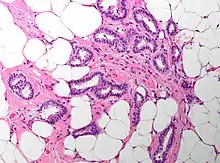

Cribriform carcinoma of the breast showing a cribriform area | |

Invasive cribriform carcinoma of the breast (ICCB), also termed invasive cribriform carcinoma, is a rare type of breast cancer that accounts for 0.3% to 0.6% of all carcinomas (i.e. cancers that develop from epithelial cells) in the breast.[1] It originates in a lactiferous duct as opposed to the lobules that form the alveoli in the breasts' mammary glands (lobules make the milk which the ducts channel to the breast's nipple). ICCB was first described by Dixon and colleagues in 1983 as a tumor that on microscopic histopathological inspection had a cribriform pattern,[2] i.e. a tissue pattern consisting of numerous "Swiss cheese"-like open spaces and/or sieve-like small holes (see adjacent Figure).[3] The latest edition (2019) of the World Health Organization (2019) termed these lesions invasive cribriform carcinomas indicating that by definition they must have a component that invades out of their ducts of origin into adjacent tissues. In situ ductal cancers (i.e. cancers localized entirely within their tissues of origin) that have a cribriform histopathology are regarded as belonging to the group of ductal carcinoma in situ tumors.[4]

The microscopic histopathology of ICCB tumors stained with hematoxylin and eosin shows cribriform areas covering more than 50% of the tumor with the remaining tumor areas showing tubular and/or other histopathological patterns. The cribriform areas consist of small-sized cells with amphophilic (i.e. taking up both the hematoxylin and eosin stains) cytoplasm, indistinct cell boundaries, and small-to-medium sized nuclei that are surrounded by a sharp nuclear membrane and contain finely stippled chromatin (i.e. DNA coated with protein).[17] Numerous open spaces and/or sieve-like small holes lie between these cells (see above photomicrograph) to give the lesions a Swiss cheese-like appearance. The spaces and holes may contain microcalcifications and/or mucins (i.e. high molecular weight, sugar-linked proteins normally produced and secreted by the mammary gland and found in milk).[3] The cells around these spaces and holes sometimes have "apical snouts", i.e. small protrusions on the side of the cells that faces the spaces and holes.[11] Tubular areas (see adjacent photomicrograph of a tubular carcinoma) consist of well-formed tubules lined with mostly normal appearing tubular cells.[17][20] The other histopathological patterns that may occur in these tumor types include the pattern associated with invasive carcinoma of no special type[4] or in uncommon cases the pattern associated with mucinous carcinoma of the breast.[17] The invasive component of these tumors almost always has the cribriform histopathology pattern.[14] All of the tumor cells in ICCB are typically slow-growing as evidenced by their low mitotic index (i.e. the ratio of the number of dividing cells to the total number of tumor cells) or low levels of cellular Ki-67 protein (an index of cell proliferation).[14]